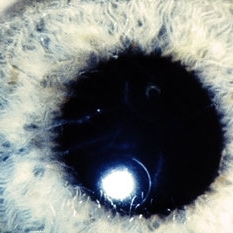

Slide 7-44

Feb 25 2019 by Lancaster Course in Ophthalmology

The entire cornea shows a diffuse haziness in the macular dystrophy.

Condition/keywords: cornea, macular dystrophy